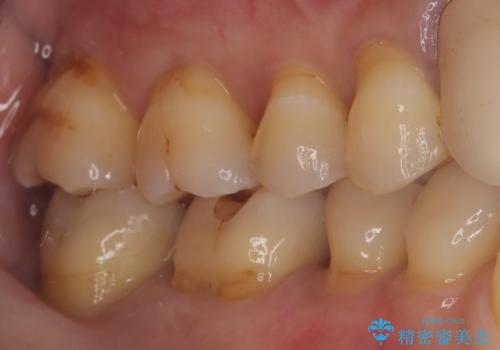

- 主訴:プラスチックの劣化が気になる。

咬合面にCR(コンポジットレジン)修復が広範囲にされており、劣化のしにくさや審美性からセラミックインレーでのやり替えとなりました。

今回残存歯質量から破折のリスクを説明し、クラウンでのやり替えも提案しましたが歯質切削量が多くなることから一度インレーで様子を見ることとなりました。